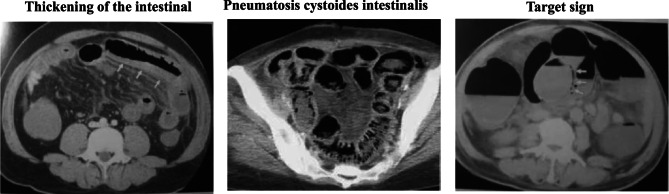

Results: From 136 initially identified cases, 117 met the inclusion criteria (91 females, 26 males; female-to-male ratio 3.5:1). The mean age was 65.2 ± 13.6 years, with 65.8% of patients aged ≥ 60 years. Underlying disease were present in 86 patients, predominantly hypertension, cerebrovascular disease, type 2 diabetes mellitus, and coronary artery disease. Medication history was significant in 69 patients, with antihypertensive, antiplatelet, statin, and hypoglycemic agents being most common. The primary presenting symptom in 81 patients (69.2%) was abdominal pain accompanied by hematochezia. Clinical staging analysis revealed significant associations with elevated neutrophil counts, increased C-reactive protein(CRP) levels, positive computed tomography findings, and CAR (C-reactive protein to albumin ratio) values. Age-stratified analysis demonstrated significant correlations with underlying disease.